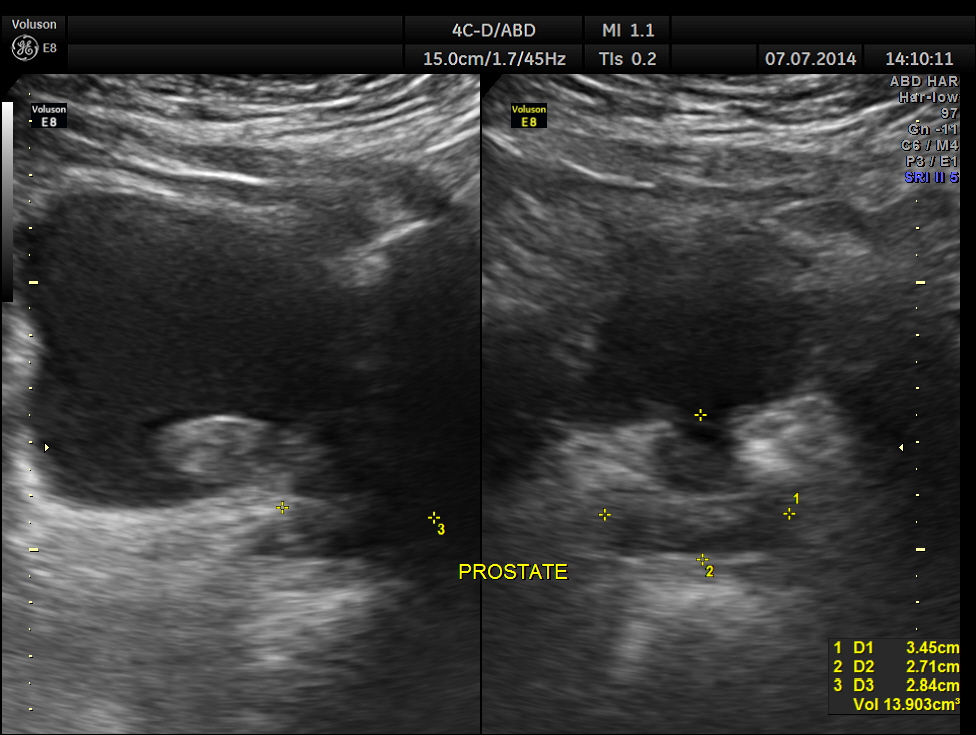

His ultrasound showed the following :

The mass measurements are given below.